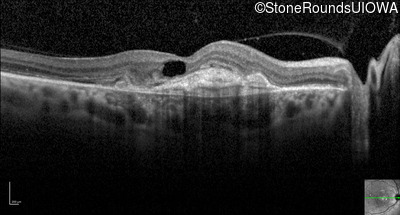

Optical Coherence Tomography - Right - 20/80 +1

Exemplar / OCT Stack